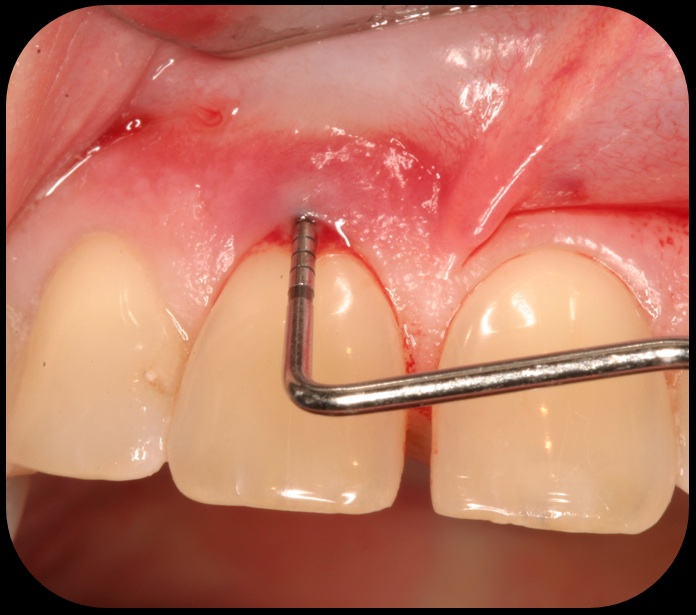

Severe periodontitis lesion.

Fig. 2